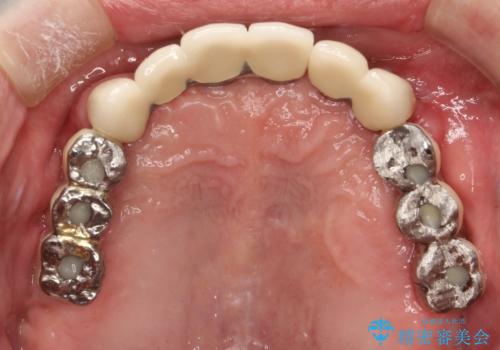

費用・時間は多大にかかりましたが、今後しっかりと咬んで生活することができるでしょう。

かみ合わせの力が非常に強く、夜間の歯ぎしり・食いしばりもひどかったため、奥歯はメタルオクルーザルの設計でかぶせ物を製作しています。

インプラントの種類:Bicon / Zimmer spline

かぶせ物の種類:PFZ / PFM metal occlusal